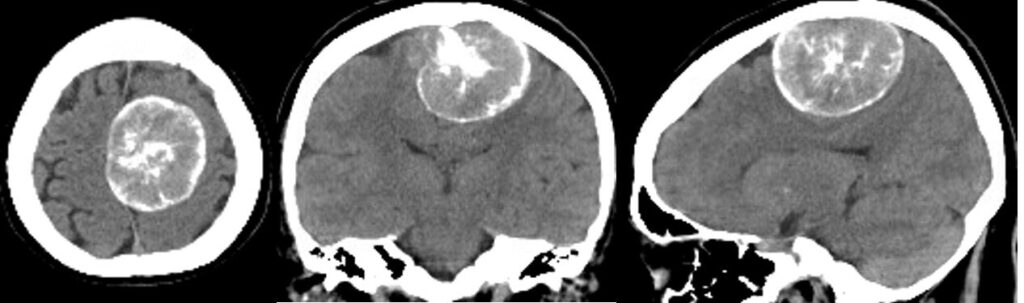

左頭頂葉の大型髄膜腫を手術しました